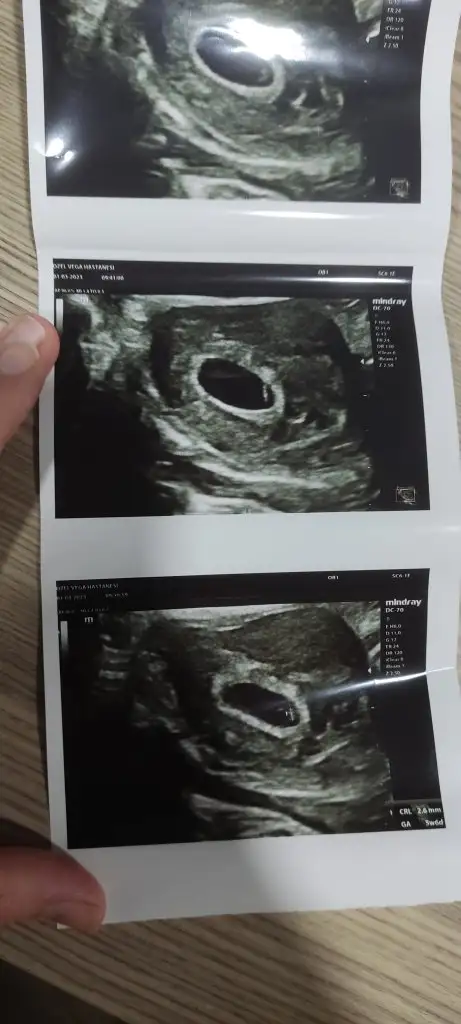

1buçuk senelik evliyim yumurtalıklarım yavaş çalışıyormuş bu ay adetimin 5 gününden 5 gün klamen kullndım ve yumurta takibine başladık sol yumurtalığım 20mm olmuş bu gün çatlatma iğnesi yaptırdım yarın akşam ilişki deddi doktor bu şekilde 1 yumurtayla hamile kalan varmı